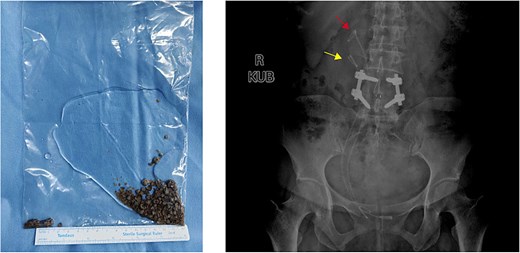

Intraoperative images revealing duplex ureter with ureterocele harboring multiple large stones. Multiple stones were discovered at the opening of ureter b and the surgery was assisted by UAS.

Holmium laser was used for lithotripsy, and the fragments were removed by negative pressure suction. Another DJ stent was placed via orifice b. The total operation time was 153 min. Postoperative KUB confirmed complete lithotripsy and correct stent in the duplex ureters (Fig. 4). The patient was discharged 3 days after surgery. All DJ stents were removed 1 month later without complications. The patient declined further examination and treatment for kidney stones and ureteral anomalies. No discomfort was reported during 6-month follow-up.